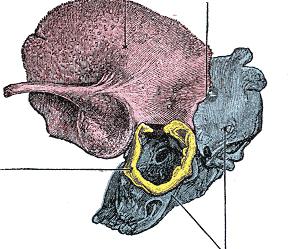

Анатомия сосцевидного отростка